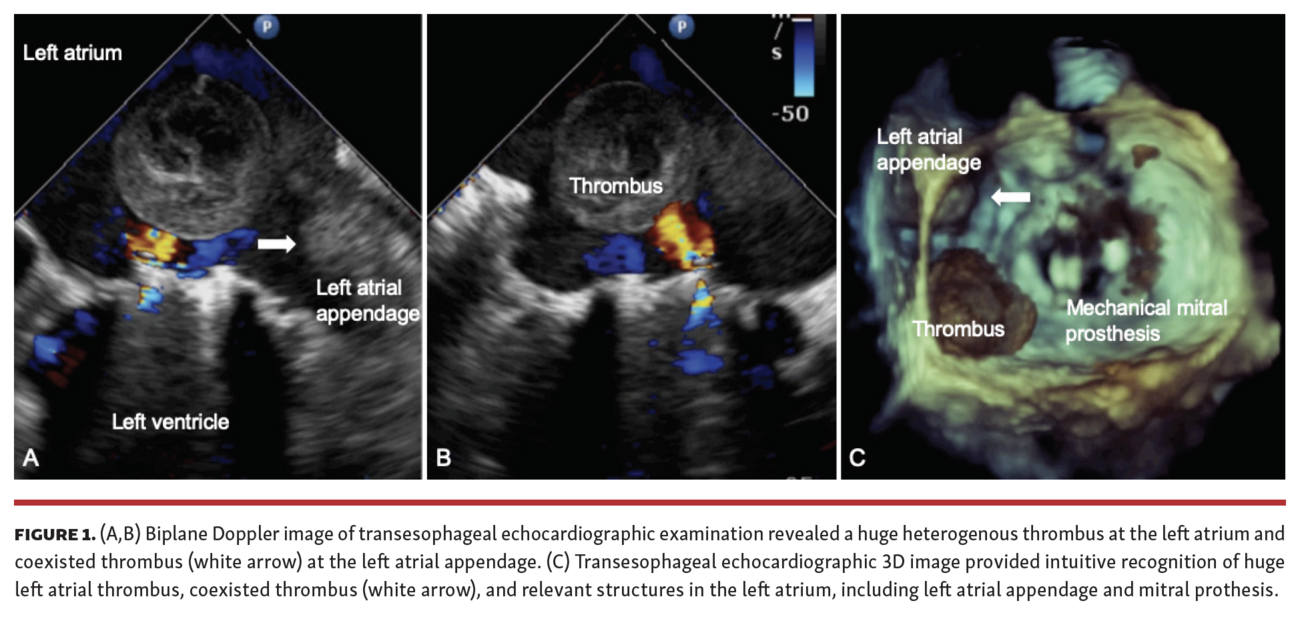

A 69-year-old woman with atrial fibrillation and rheumatic heart disease who underwent mechanical mitral replacement 20 years ago presented with sudden coma. She took warfarin regularly until 10 days prior when she developed gum bleeding. The neurologic examination revealed reduced muscle strength on the right side of the body and alteplase was administered. Then, computed tomography revealed multifocal hypodensities in the bilateral cerebellum, thalami, left parietal, and occipital lobes with thalamic hemorrhage. Anticoagulation was not given for 2 weeks until transesophageal echocardiographic examination revealed normally functioning mechanical mitral prosthesis and a 4 cm left atrial heterogenous thrombus moving around the left atrium like a ping pong ball. Also visible was a thrombus within the left atrial appendage (Figure 1A and 1C, arrow). The left atrial thrombus moved toward the mitral orifice and was bounced away by mitral regurgitant jet; it moved like a ping pong ball (Video Series). Cardiac arrest occurred 1 week after examination with successful resuscitation, presumably due to transient mitral obstruction of the huge thrombus. Her condition gradually recovered and anticoagulation has been resumed.